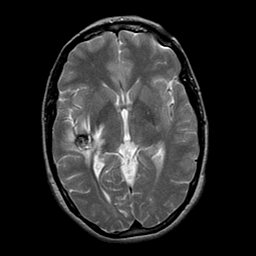

overlay -- Slice #13

[Home][Help][Clinical] Slice 13